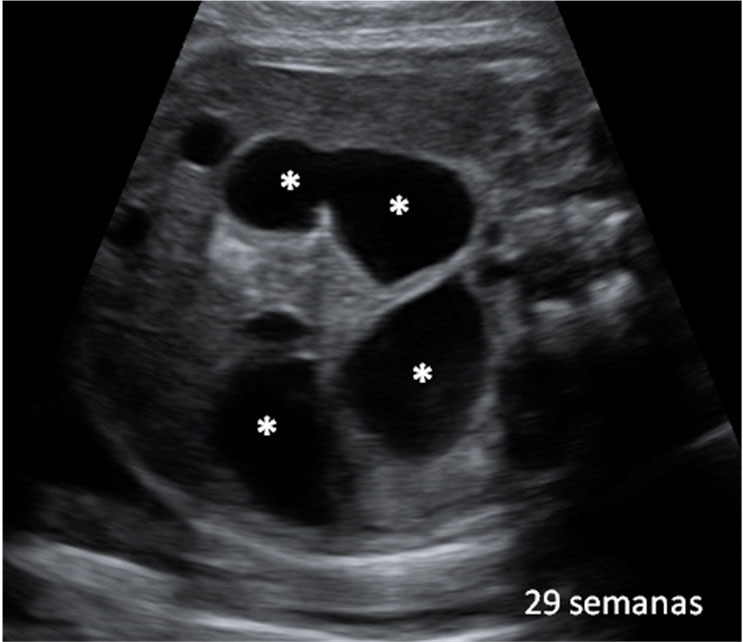

En la semana 20 de gestación, el aparato genital del feto ya es evidente, tanto en niñas como en niños con una ecografía en 4D. Los órganos genitales externos se formaron en la semana 12 de embarazo.

Cómo es el aparato genital femenino del feto en vídeo

En la imagen podemos apreciar un feto del sexo femenino con una edad gestacional de 20 semanas y 3 días.